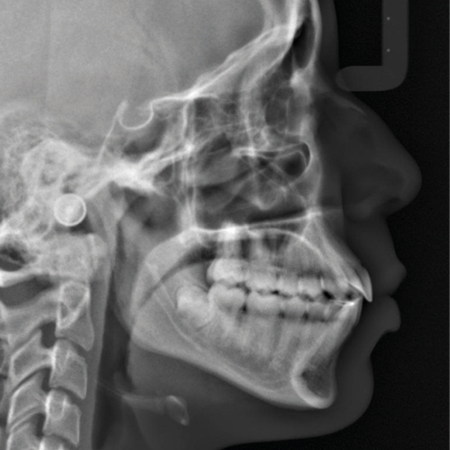

Hybrid treatment of skeletal Class II malocclusion with functional orthopaedics and Invisalign in an 11-year-old child

OBJECTIVE: This article describes the treatment of an 11-year-old child with skeletal Class II malocclusion due to mandibular deficiency, conducted in a hybrid approach. Initially she was treated with functional orthopedics using a mandibular activator, and then treatment was continued with Invisalign aligners. CONCLUSION: Total treatment time was two years and two months, and facial and dental results demonstrate the efficacy of the hybrid treatment adopted.